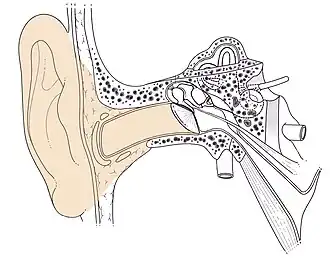

Conduit auditif externe droit Schéma